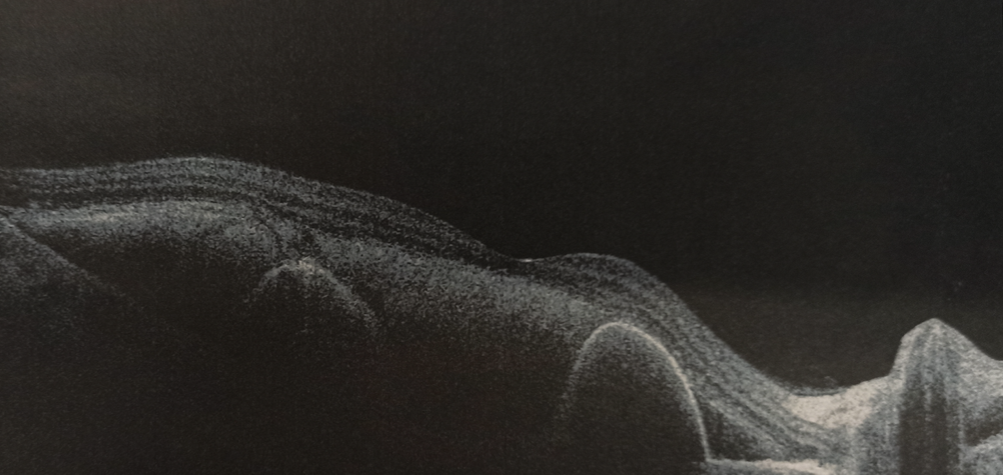

Об'єктивно - на правому оці субретинальний крововилив від аркади до аркади, з елементами субпігментного крововиливу, кров у стадії розсмоктування й у деяких ділянках фіброзування згустку.

На лівому оці друзеноїдне відшарування пігментного епітелію, ВМД (суха форма), тобто все ще попереду.

Під час операції вдалося відмити значну частину субретинальної крові, що дає право сподіватися на збереження макулярних функцій, разом з цим, згорток крові, що знаходився під сітківкою протягом 3 тижнів, вже почав фіброзуватися - такі тяжі видалити не вдалося. Ми розраховуємо на те, що такі тяжі розташовуються ближче до аркад, тому на фовеолярні функції впливати не повинні.